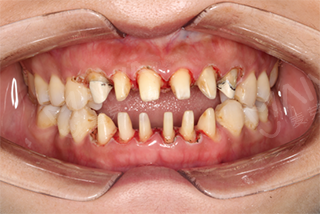

治疗前的董女士

修复前的牙齿

34岁的董女士是深圳市一家食品店的老板,由于自身工作的原因,董女士的牙齿很早便出现了问题,10年前就为自己的上下前牙做了金属烤瓷修复,但是由于平时自己疏于护理,最近牙齿牙龈发黑,为了在客户面前展现最美的笑容,董女士来到了麦芽口腔。